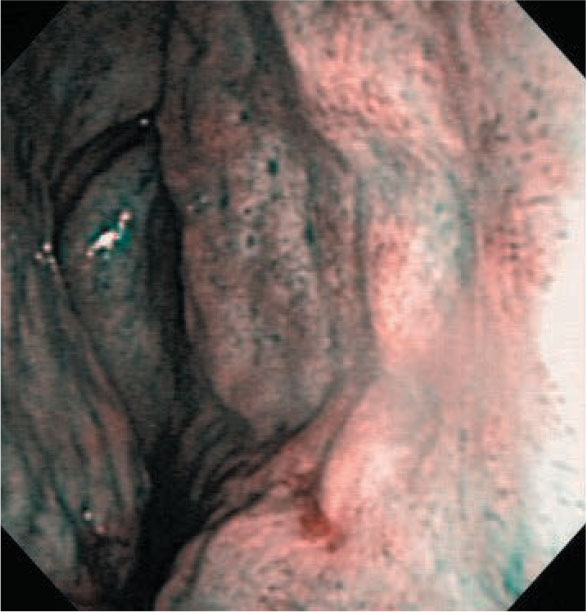

右鼻出血(高血圧性鼻出血)81歳・男性

受診1日前に出血した高血圧性鼻出血。ボスミンをスプレー処置前のNBIで鼻中隔に出血部位と思われる箇所を認めた。

しかし,ボスミンをスプレー後5分の方がはっきりと出血部位を確認できた。

通常光

NBI